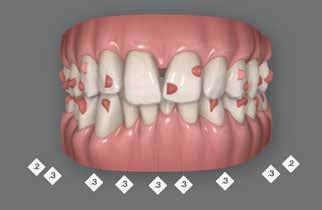

Der planlægges alignerbehandling af begge kæber med intrusion af 1+1 og 2,1-1,2, nivellering af trangstilling UK med interproksimal reduktion (IPR) (Fig. 2 A, B) og senere IPR OK for reduktion af dark triangles mellem incisiverne efter nivellering. Patienten instrueres i at benytte alignere 20-22 timer/ dag med alignerskift hver 7. dag, og patienten ses hver 3.-8. uge under forløbet. Den første alignerserie består af 16 alignere for nivellering OK/UK og IPR i UK (Fig. 2). Efter denne serie planlægges IPR mellem incisiverne i OK for reduktion af dark triangles (Fig. 3) samt yderligere intrusion af OK og UK-fronten i 12 refinement-alignere. Patienten udviser god kooperation og er meget tilfreds med alignerapparaturet, som er mindre synligt end det faste apparatur (Fig. 4).